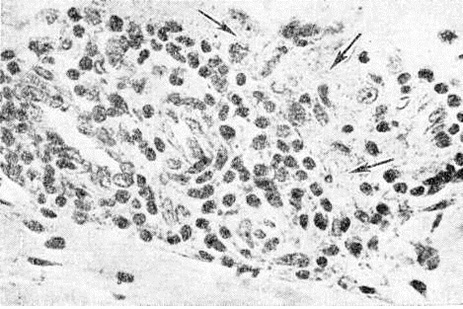

Рис. 2.

Микроскопическая картина кожного инфильтрата при лепроматозном типе лепры: стрелками указаны лепрозные клетки Вирхова с «пенистой» цитоплазмой. Окраска гематоксилин-эозином; × 640.

Рис. 1—6.

Микроскопические картины поражений при различных формах лепры.